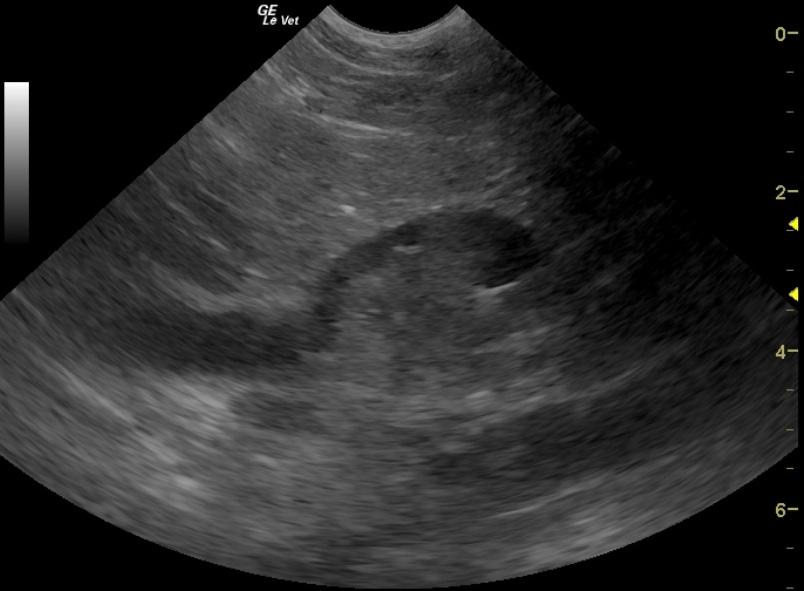

A 10-year-old FS mixed breed dog was presented with a history of polyuria, polydypsia, and urinating in the house. Physical examination was non-remarkable. Urinalysis showed isosthenuria, 1+ proteinuria, 2+ hematuria, and struvite crystals. Abnormalities on CBC and blood chemistry were leukocytosis as a result of neutrophilia, monocytosis and basophilia, thrombocytosis, elevated AST, elevated ALT, and elevated GGT activity, and marked elevation of ALP activity. The patient had been treated with Amoxicillin.

A 10-year-old FS mixed breed dog was presented with a history of polyuria, polydypsia, and urinating in the house. Physical examination was non-remarkable. Urinalysis showed isosthenuria, 1+ proteinuria, 2+ hematuria, and struvite crystals. Abnormalities on CBC and blood chemistry were leukocytosis as a result of neutrophilia, monocytosis and basophilia, thrombocytosis, elevated AST, elevated ALT, and elevated GGT activity, and marked elevation of ALP activity. The patient had been treated with Amoxicillin.